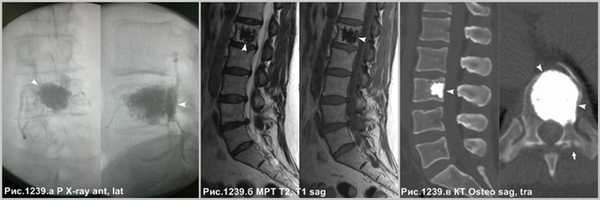

Итраоперационный рентгеновский контроль, посредством электронного оптического преобразователя, демонстрирует компактный участок плотного медицинского цемента, выполняющего полость крупной гемангиомы (головки стрелок на рис.1239.а), после вертебропластики, призванный стабилизировать тело пораженного позвонка и предотвратить вероятность патологического перелома. Следы вертебропластики в виде участка остеосклероза на МРТ (головки стрелок на рис.1239.б) и на КТ (головки стрелок на рис.1239.в). Визуализируется канал от прохождения иглы в левой дужке позвонка (стрелка на рис.1239.в).